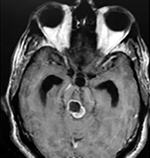

Cortes axiales en ponderación T1, cambios postquirúrgicos.